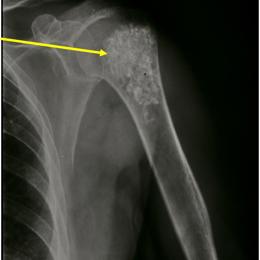

Radiographic imaging is used to help form a diagnosis. These include X-Ray, MRI, CT and Bone Scans

An example of an enchondroma X-Ray is shown.